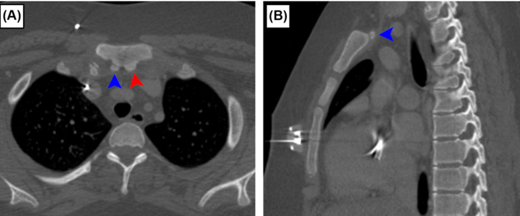

此外,胸骨的正常变异也不容忽视。上胸骨小骨 是一种存在于约1.5%人群中的正常变异,在亚洲人群中发生率更高(约3.8%)。如图A(轴位视图)和图B(矢状位视图)所示,这些小骨位于胸骨柄后方,可能与胸骨柄完全分离,进一步增加了左头臂静脉前方受压的风险。

图A & 图B:上胸骨小骨(EO)的解剖位置